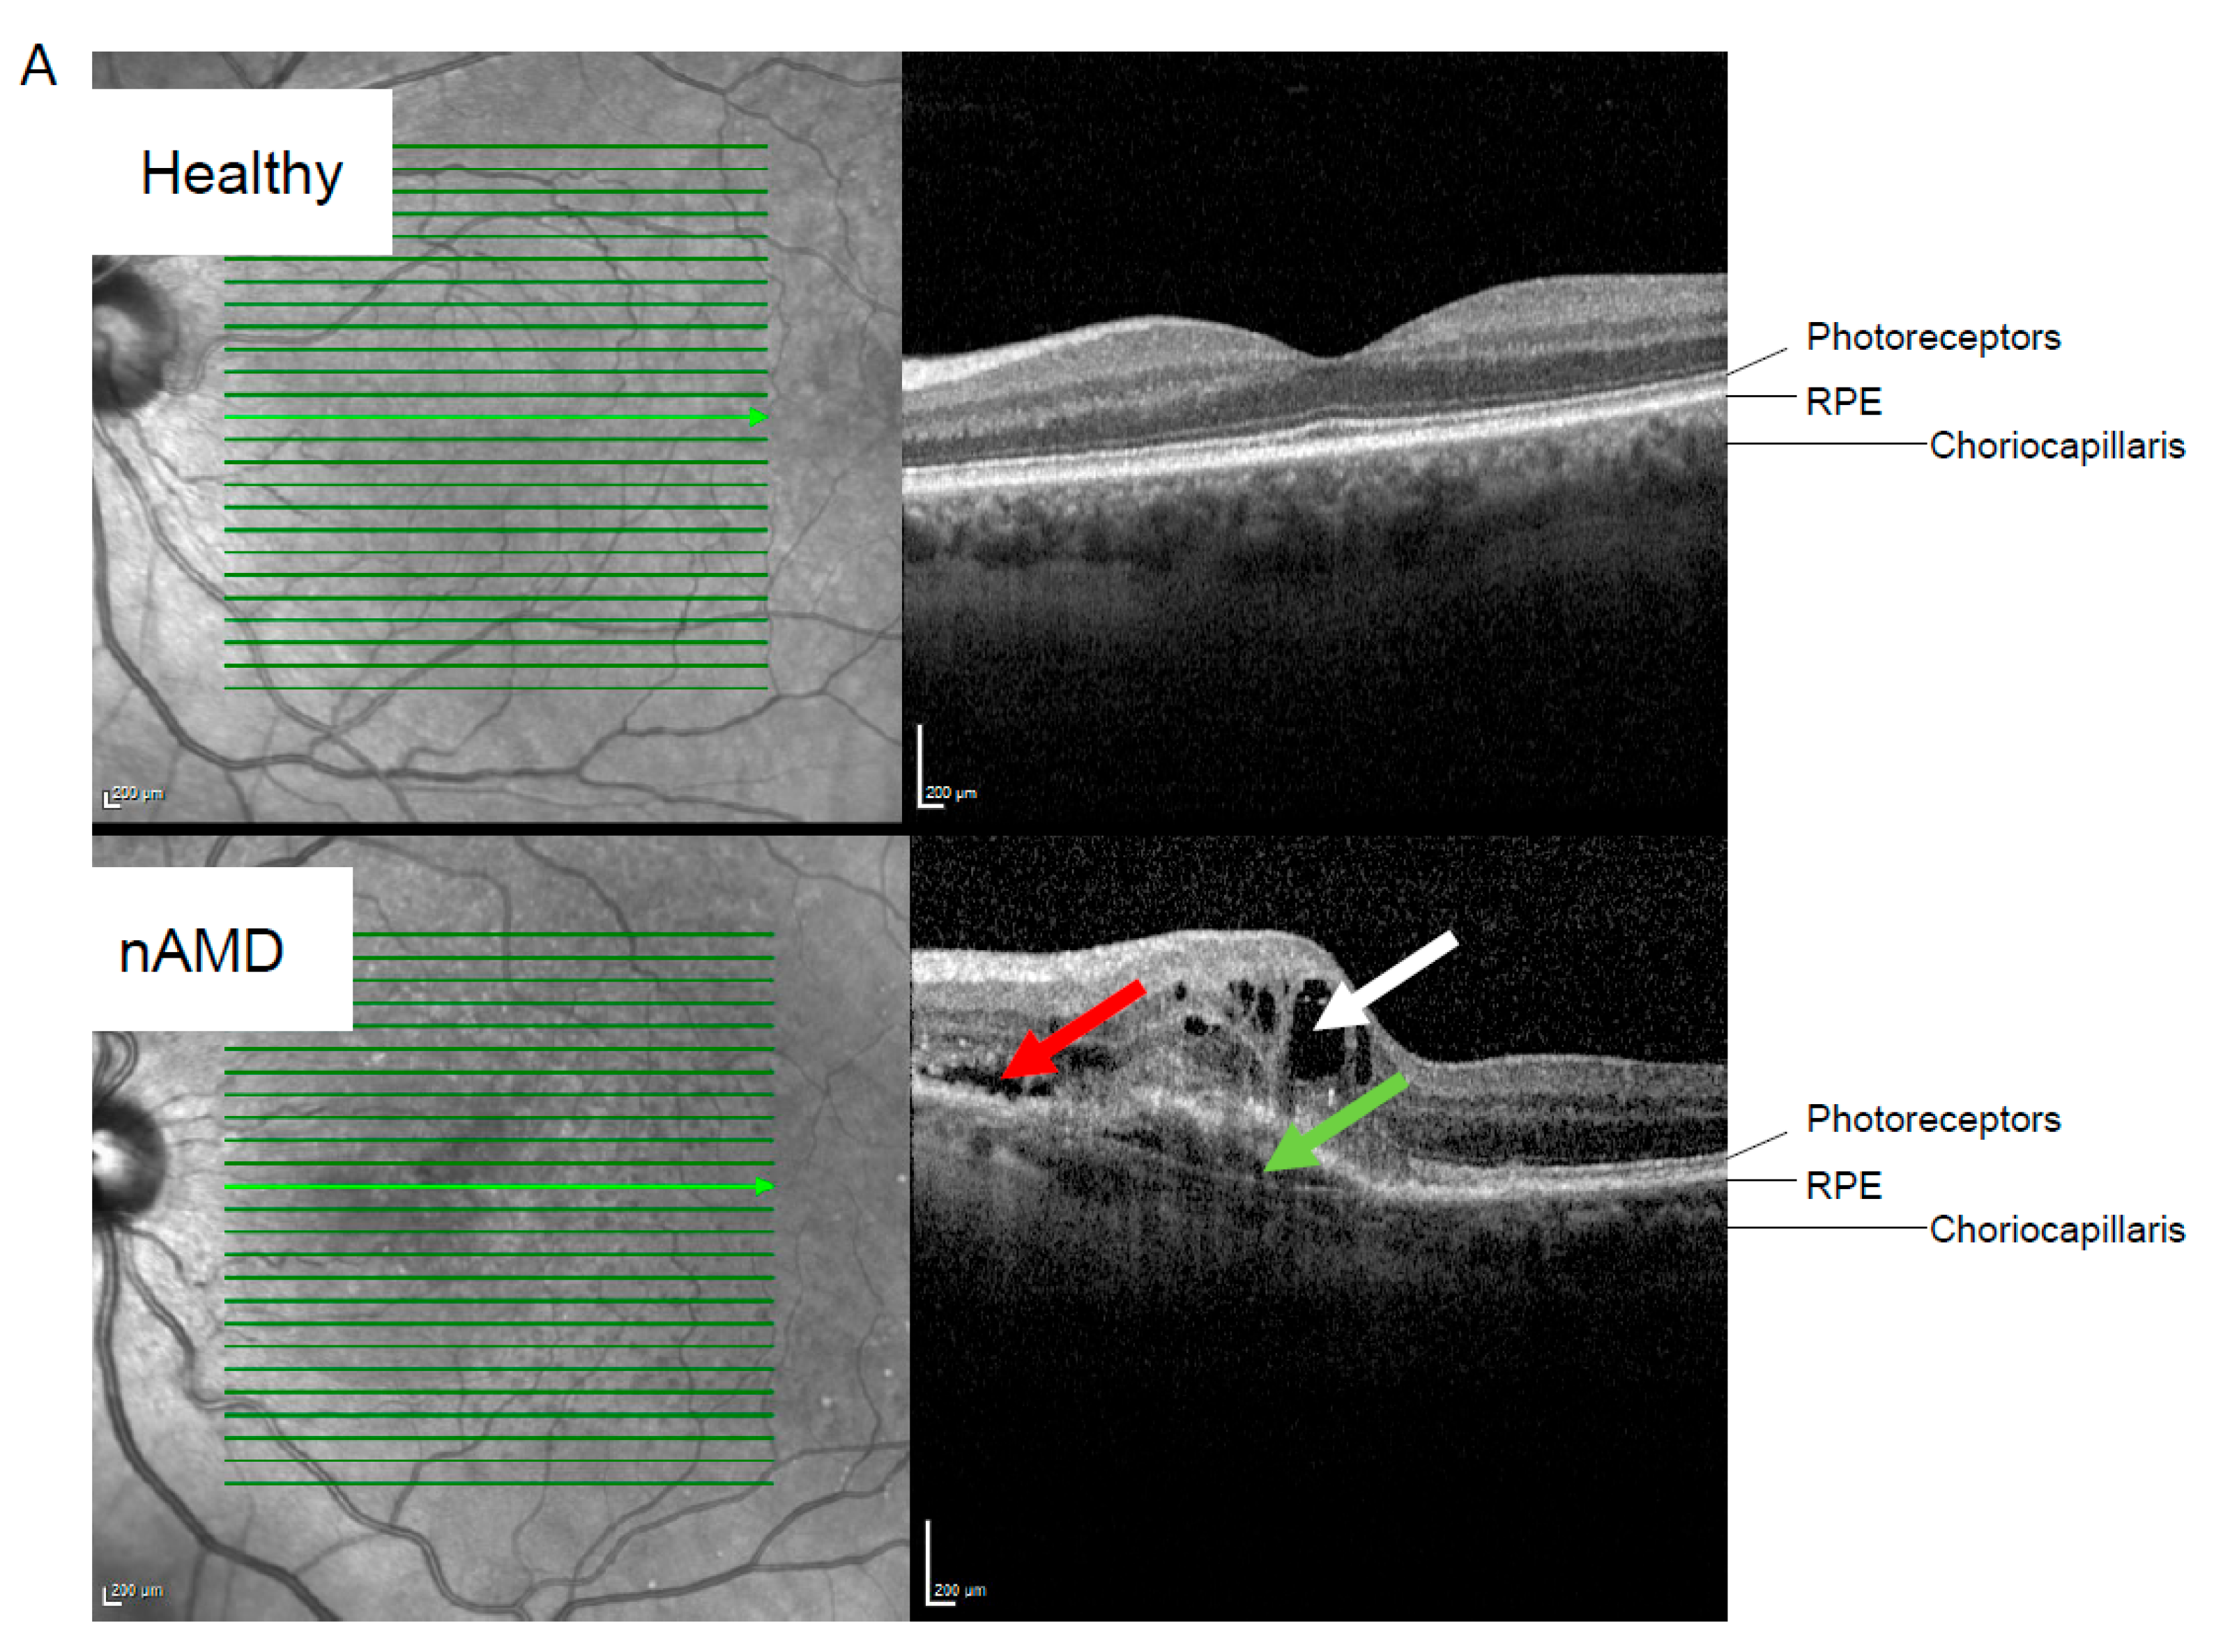

2.2. RNA Profile Linked to nAMD Progression